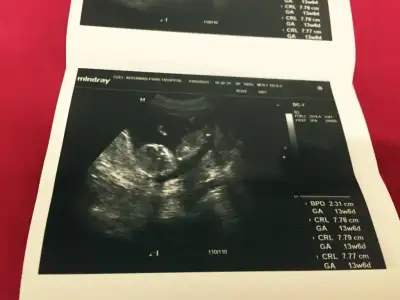

Kizlar bnm bebisimede bakarmisinz rica etsem,doktor 16.haftayibekle dedi,biz 13. Haftadayiz..

o gördüğümüz nub ise açılı sanırım erkekKizlar bnm bebisimede bakarmisinz rica etsem,doktor 16.haftayibekle dedi,biz 13. Haftadayiz..

Cnm bu en son foto 13+6, bunada baksana daha net bu foto..Canım ilk fotografa bakmamıştım bebek tam yan değil hafif arkası dönük sidellanın tahmini doğru sanırım...